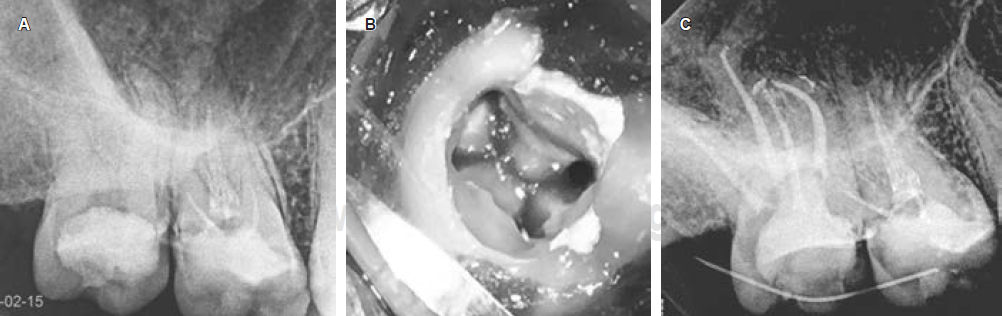

Se presentó una mujer de 28 años de edad con antecedentes médicos no contributivos con dolor a los cambios térmicos en el segundo molar maxilar derecho. Clínicamente, se observó la presencia de una amalgama fracturada y caries profunda. Desde el punto de vista radiográfico, el ancho del espacio del ligamento periodontal (PLS) era normal y no había patología periapical. Hubo una respuesta prolongada al frío y una prueba de percusión vertical positiva, con ausencia de bolsas periodontales. El diagnóstico pulpar fue pulpitis irreversible sintomática y el diagnóstico periapical fue de periodontitis apical sintomática. Después de la técnica de anestesia local con lidocaína con epinefrina al 1:80,000, el tratamiento se realizó con aislamiento absoluto con dique de hule y aumento con lupas (3.5x).La amalgama se retiró con fresas de diamante y luego la cavidad de acceso se diseñó con fresas de carburo y puntas ultrasónicas Star X (Dentsply Sirona). La cavidad de acceso tenía un diseño cuadrangular y se ubicaron cuatro conductos radiculares. Cada uno de los cuatro conductos se negoció una lima k10/02 (Dentsply Maillefer, Ballaigues, Suiza) precurvada. Se tomó la longitud de trabajo con un localizador de ápices (Root ZX, J. Morita, Tokio, Japón) y se confirmó con una radiografía dentoalveolar digital. Para la instrumentación de los conductos radiculares se usó el sistema Mtwo® (VDW, Alemania). Los conductos vestibulares fueron instrumentados a 35/04 y los dos conductos palatinos a 40/04. El protocolo de irrigación y la técnica de obturación fueron los mismos que en el caso anterior (Figura 2A-E).

Figura 2 Caso 2. A) Radiografía preoperatoria. Presencia de amalgama con proximidad a la cámara pulpar, no hay signos de patología periapical. B) Canales radiculares vestibulares. C) Canal radicular de mesiopalatina. D) Canal radicular distopalatino. E) Radiografía postoperatoria inmediata, se observa la presencia de cuatro raíces.

La identificación radiográfica preoperatoria de una raíz adicional tiene algunas dificultades. Estas dificultades pueden incluir la superposición de estructuras anatómicas como se observa en las radiografías preoperatorias de los dos casos presentados.13 Si el contorno de las raíces no se observa claramente en una radiografía, se deben tomar más radiografías con diferentes angulaciones para identificar o descartar la presencia de variaciones anatómicas (Figuras 1A y 2B). Algunas de las técnicas de angulación para tomar radiografías han sido revisadas previamente por Fava y colaboradores.13 Las radiografías siempre tendrán ciertas limitaciones, independientemente de las técnicas de angulación utilizadas, la imagen radiográfica es una sombra y es una representación bidimensional de un objeto tridimensional.14 A pesar de estos desafíos, las radiografías dentoalveolares preoperatorias de buena calidad podrían ser muy útiles en la identificación de características radiográficas (como la lámina dura y el ligamento periodontal) que pueden interpretarse de manera más consistente que otras15 y que nos puede proporcionar información para una mejor determinación del número y la forma de las raíces en los molares superiores.16 Cuando las raíces de los dientes parecen ser más largas que la longitud promedio (20 mm) o la longitud máxima (24 mm), esto puede ser una indicación de una raíz adicional (Figura 1A-C ). Por ejemplo, algunos casos reportan segundos molares maxilares con dos raíces palatinas con una longitud de la raíz palatina igual o superior a 26 mm.17 Por lo general, utilizando la técnica de ángulo de bisección estándar, la raíz palatina se puede ver detrás y en el medio de la raíz distobucal y mesiobucal en una radiografía. Si la raíz palatina no se pudiera identificar en la posición mencionada anteriormente (Figuras 1A y 2A), esto sería una indicación de una variación anatómica como la presencia de una raíz palatina adicional. Para una correcta identificación de la raíz palatina en esta situación es aconsejable tomar más radiografías que modifiquen la angulación vertical u horizontal para obtener una imagen no superpuesta de las estructuras de interés (Figuras 1C y 2C). La radiografía de la longitud de trabajo también puede confirmar la presencia de dos raíces palatinas si el instrumento parece estar alejado del centro de la raíz.18,19